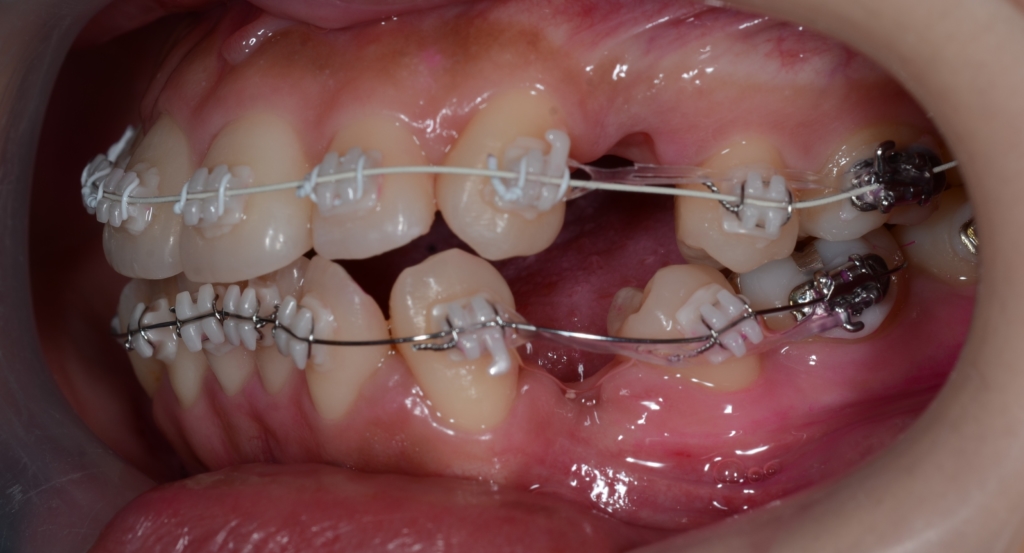

治療は進み、前歯が引っ込んで、かつ、しっかり噛めて問題ないのですが、唯一上下の正中(真ん中)がズレている状況でした。

そこで、真ん中を合わせるために、口蓋にアンカースクリューを植立して「力」を加えることにしました。

約2か月、期間を空けてアンカースクリューが落ち着いたところで、PLASという付属品を付けて、上下の正中を合わせるように試みます。